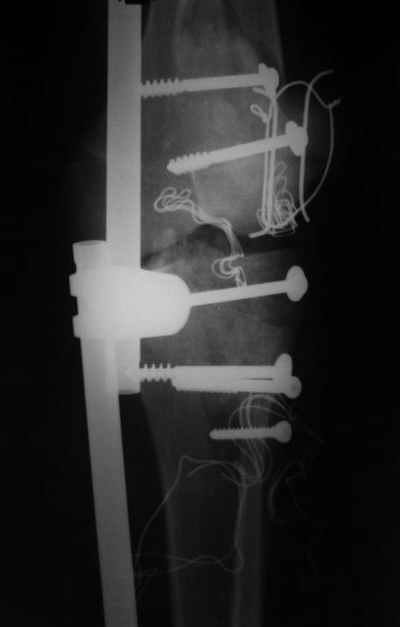

Отправитель: Evgueny Tschekashkin 14 Декабрь 2004, 18:41

Вид раны на сегодня...

4 cутки после травмы.

Спасибо за комментарии. Травма тяжелая с проблематичным прогнозом для функции коленного сустава( изначально травма разгибательного аппарата с последующим частичным некрозом собственной связки надколенника и о обнажением рефиксированного фрагмента бугристости большеберцовой кости, дефектом центрального отдела суставной поверхности большеберцовой кости и медиального отдела капсулы сустава).